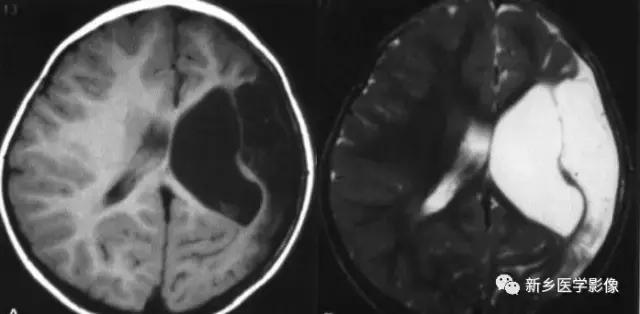

(2)脑裂畸形:胚胎期脑的发育经历6个主要阶段:①背侧诱导阶段;③腹侧诱导阶段;③神经增生阶段;④神经元移行阶段;⑤组织形成阶段;⑥髓鞘形成阶段。脑裂畸形发生在神经元移行阶段。脑裂畸形可累及一侧或双侧大脑半球,脑裂畸形位于侧面.常累及中央前、后回区偶尔位于大脑半球的其他部位。脑裂畸形的裂隙可以很窄,裂隙两侧灰质紧密相贴,称闭合型。裂隙也可以很宽,中间为脑脊液,分离型。

分离型脑裂畸形需要与脑穿通畸形囊肿鉴别.脑裂畸形的裂隙两旁一定为一灰质结构,而脑穿通畸形囊肿周围无脑灰质包绕。裂隙两旁是否为灰质结构是区别脑裂畸形与脑穿通畸形囊肿的可靠征象。裂隙两侧的灰质可不正常,可呈多小脑回样。脑裂畸形也可合并脑灰质异位。

分离型在CT很容易显示.闭合型有时容易漏诊.MRI对裂隙两侧的灰质结构容易辨认。脑裂畸形常合并透明隔缺如.侧脑室扩大,脑裂畸形处脑室边缘不规则.常可见指向裂隙的裂或 三角形憩室存在。